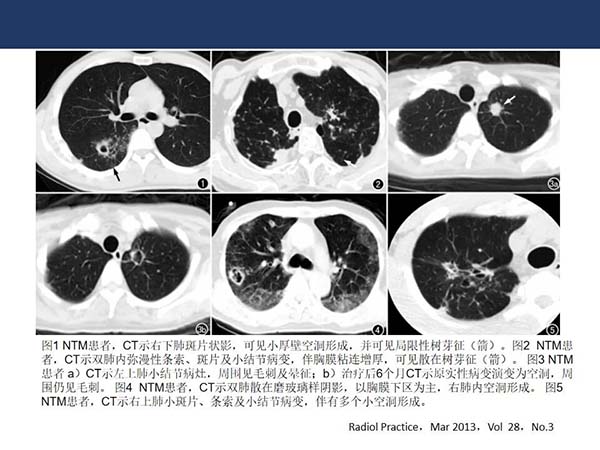

【杨柳病例】非结核分支杆菌肺病(NTMPD)